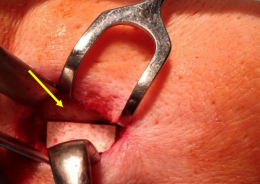

A macroscopic image of the implantation site of the ceramic plate after 6 months of healing since the surgery shows the resorption and complete integration of the implant into the new bone tissue

The effectiveness, healing efficiency and quality of developed biomaterials in preclinical research were monitored by M. Giretová, R. Štulajterová (ÚMV SAV) and L. Krešáková (ÚVLF) on large animal models. A ceramic plate made of innovated biomaterial was implanted in the pig's jaw-bone. The biomaterial was gradually resorbed at the site of the defect and successfully replaced with new bone tissue characteristic of complete bone tissue regeneration.